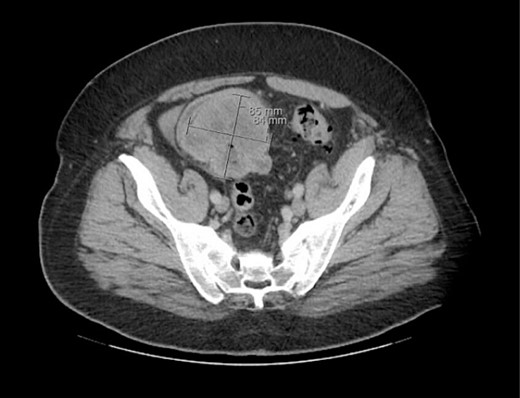

The patient was initially managed nonoperatively with conservative measures including nasogastric (NG) tube decompression, pain control, and serial abdominal exams. Surgery was consulted once CT imaging was obtained (Figs 1–3) and recommended that the patient undergo surgery to resect the identified mass and relieve the obstruction. During the surgical exploration, a mass originating from the terminal ilium was identified that was densely adhered to the peritoneum, bladder, and sigmoid colon, requiring careful dissection. The mass, three lymph nodes, and 29 cm of associated small bowel segment was resected with grossly negative margins, with the mass measuring 7 cm × 8 cm × 9.5 cm. A side-to-side anastomosis was created and the specimens were sent to pathology for further investigation. Postoperatively the patient was hospitalized for 7 days for pain control and monitoring. On postoperative day eight he was discharged with follow up appointments with oncology, general surgery, and a referral to an academic cancer center.

Initial CT imaging, axial cut, showing necrotic mass causing small bowel obstruction.